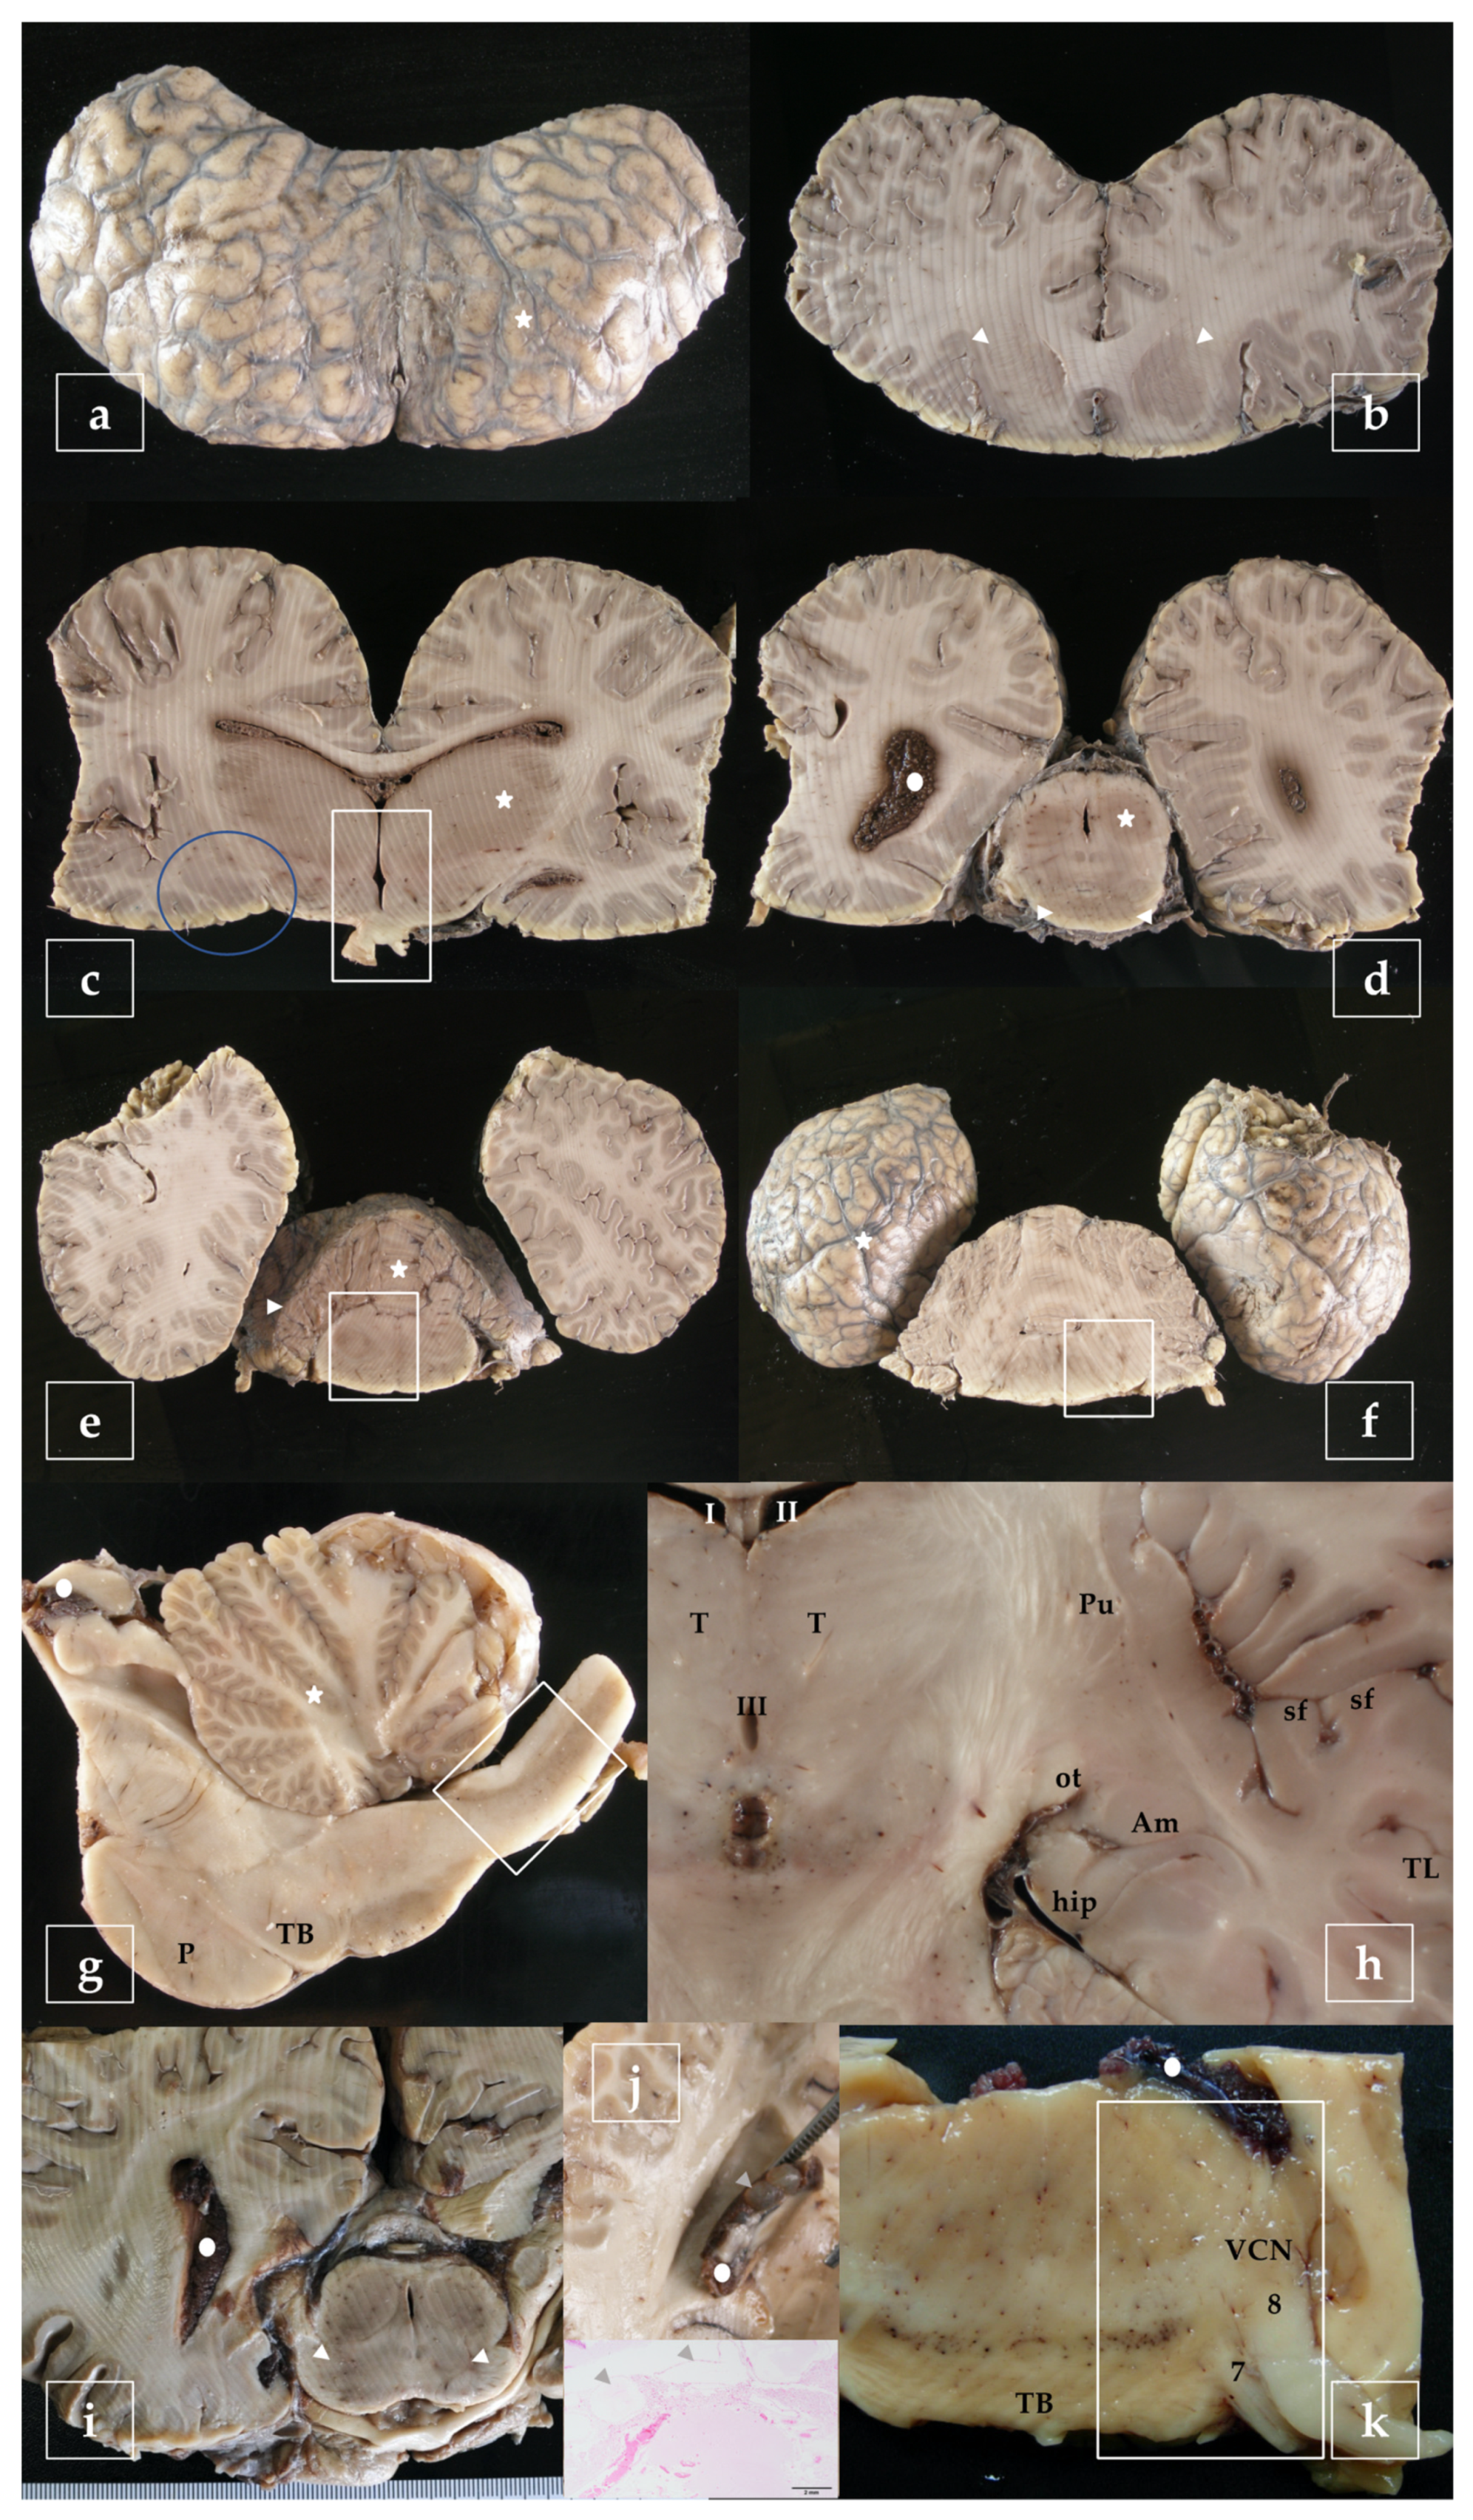

- telencephalon: cortex (2 to 4 samples, at least frontopolar and occipital cortex) (a and f, stars), corpus striatum (b, arrowheads), amygdala (c, blue circle; h, Am), and hippocampus (h, hip);

- diencephalon: thalamus and hypothalamus (c, star and rectangle);

- mesencephalon: tectum (colliculus rostralis and caudalis) (d, star) and tegmentum (with the substantia nigra) (d and i, arrowheads);

- rhombencephalon: at least pons (with the locus ceruleus) (e, rectangle), trapezoid body (with the cochlear nuclei) (f and k, rectangle), medulla oblongata (g, rectangle) and at least two samples of the cerebellum (included a sagittal section of the vermis) (e and g, arrowhead and star);

- choroid plexus (d, g, i, j, and k, circle);